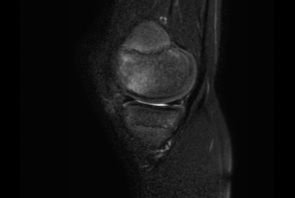

Болезнь или синдром Гоффа — это патологическое состояние, которое характеризуется развитием воспалений жирового тела вокруг сустава колена. Негативные изменения сопровождаются нарушением функциональной активности суставного сочленения, болями, хрустом, выбуханием по обеим сторонам связки надколенника и повторными скоплениями жидкости в суставе.